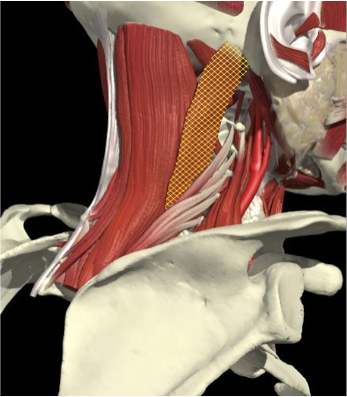

ACCURACY OF LOCALIZATION - SCALENES

ACCURACY OF LOCALIZATION LEVATOR SCAPULAE

LOCALIZATION OF MUSCLES IN DEEPER LAYERS

Layer 1

Layer 2

Layer 3

Splenius Capitis

Semispinalis Capitis

Longissimus Capitus

Semispinalis Cervicis

ACCURACY OF LOCALIZATION – DEEPER LAYERS